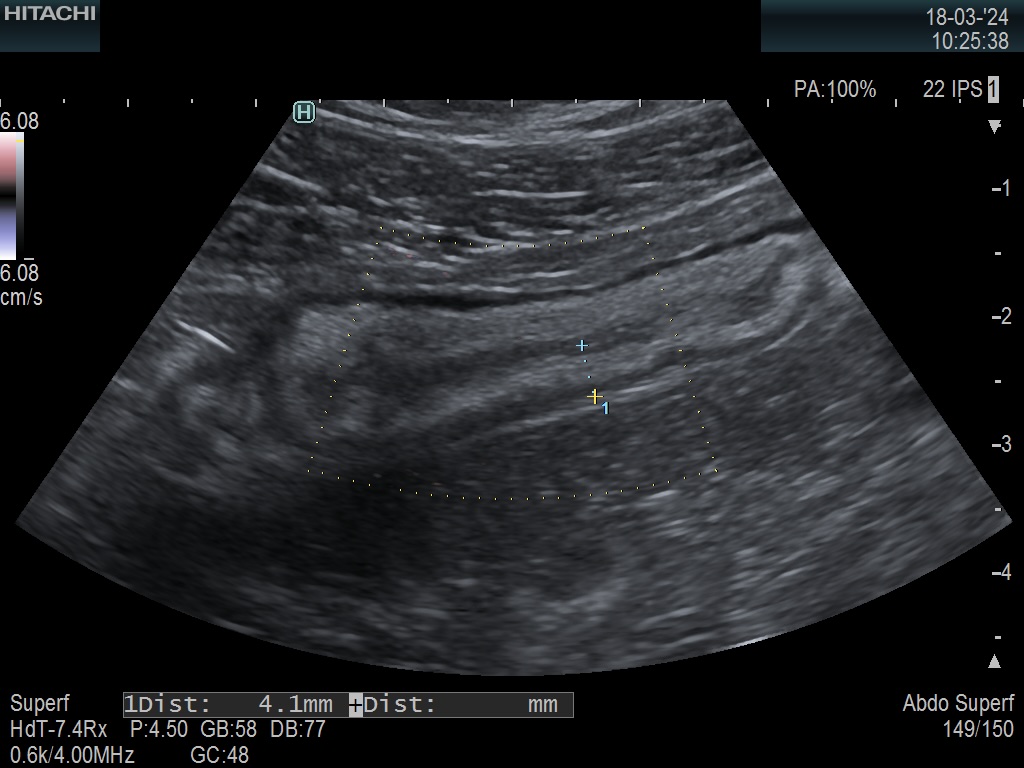

Paroi 4,1 mm et Doppler négatif (Limberg 0)

Score de Milan = 5,74 (1,4 x4,1 +0)

Donc la maladie va mieux, l'évolution est favorable

Mais la maladie reste active (non cicatrisée).